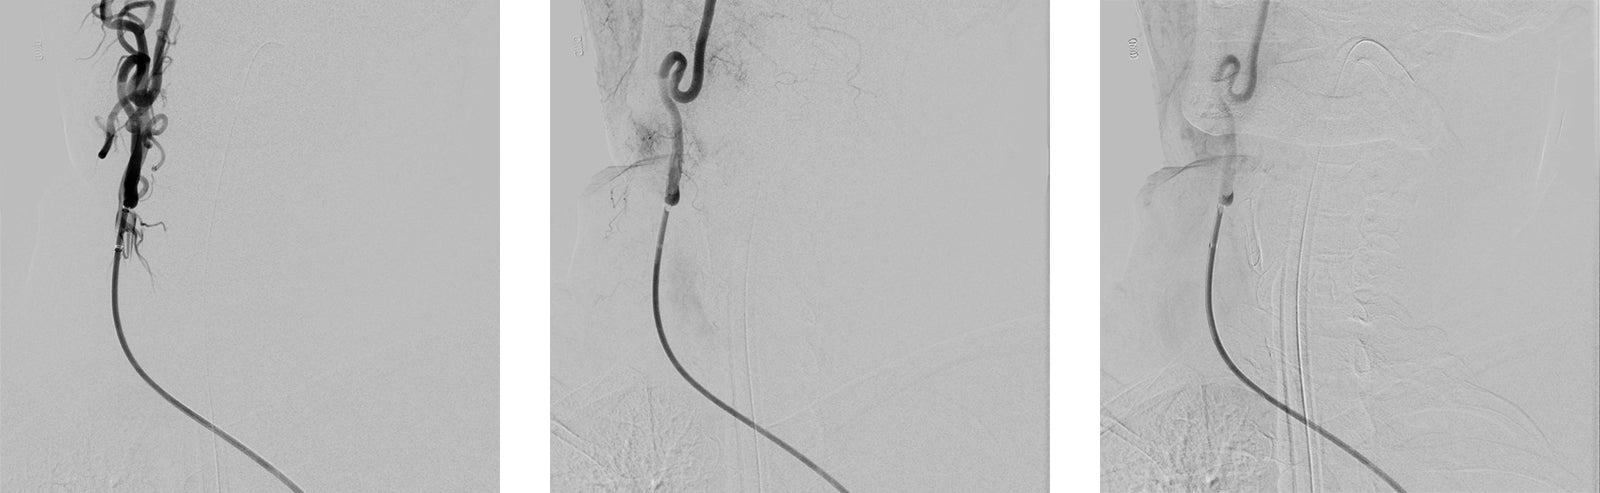

Intra-arterial mechanical thrombectomy is a minimally invasive procedure that, when performed in conjunction with Alteplase administration, can remove clots and stop a stroke in its tracks.

During a mechanical thrombectomy, a neurosurgeon uses an innovative, catheter-based technology to capture the clot and pull it out of the artery, which immediately restores blood flow to the brain. This procedure is enhanced by biplane technology, an advanced imaging system that helps the physician guide instruments through the patient’s artery to the clot.

Images of clot removal with Intra-arterial mechanical thrombectomy

Hill says, “During this procedure, he was noted to have severe stenosis in his right internal carotid artery with thrombus. The neurointerventional team had fully successful clot retrieval and placed a right carotid artery stent to open and stabilize this artery. This diseased artery was likely the cause of his stroke.”